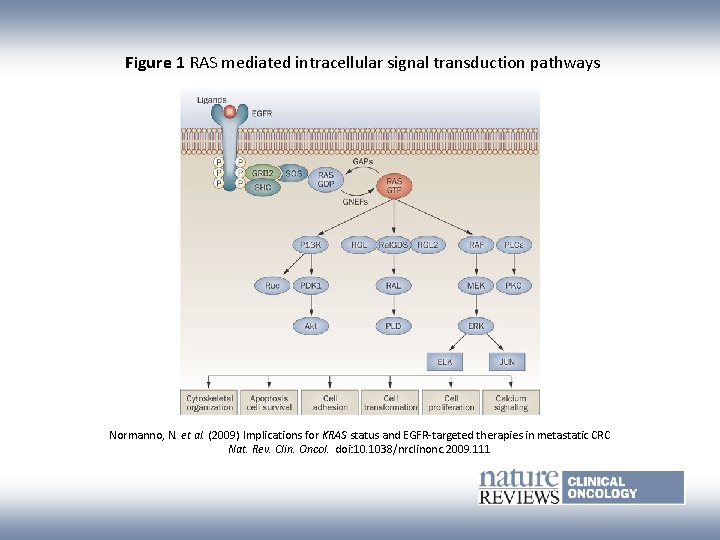

Figure 1 RAS mediated intracellular signal transduction pathways Normanno, N. et al. (2009) Implications for KRAS status and EGFR-targeted therapies in metastatic CRC Nat. Rev. Clin. Oncol. doi: 10. 1038/nrclinonc. 2009. 111

KRAS Sequencing: What Drugs Not to Use Ø 21 -k. Da GTPase involved in signal transduction in MAPK pathway Ø Mutations are common in human cancer including in: 90% pancreatic ca, 50% colon ca, 30% lung NSCLC Ø Mutations in KRAS are “downstream” of EGFR; such tumors would not respond to anti-EGFR therapy EGFR